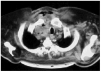

During the study period we treated 26 cases (20 men and 6 women) for acute mediastinitis. The mean age of the patients was 55 years (range 2685 years). In 17 cases (64%) mediastinitis originated in the esophagus: 8 (30%) occurred after resection of esophageal carcinoma and 9 (34%) were secondary to esophageal perforation. Four of the perforations were due to spontaneous rupture (Boerhaave syndrome), 4 were iatrogenic, and 1 was caused by ingestion of a foreign body (a lamb bone). In 6 cases (23%), the cause was oropharyngeal infection due to dental or peritonsillar abscess (Figure), and 3 cases (12%) were secondary to median sternotomy wound infection. Mediastinitis was associated with pleural empyema in 20 cases (76.9%) and with peritonitis in 1 case (3.5%). All diagnoses were confirmed by computed axial tomography. In the cases with infection originating in the esophagus, contrast-enhanced images were obtained to locate the perforation site. Diagnosis was reached within 12 hours in 15 cases (56.7%) and within 24 hours in 8 (30.8%). Diagnosis and, therefore, treatment were delayed for the remaining three patients (12.5%). All the patients underwent thoracotomy except one who was treated by means of chest tube drainage. In addition to mediastinal debridement and drainage, 10 patients underwent esophagectomies or resection of the esophago-gastric reconstruction (deferring a new reconstruction), 5 received primary sutures of the esophagus covered with an intercostal muscle or pericardial fat flap, 1 was reconstructed with a greater pectoral muscle flap, and 1 underwent sternectomy plus intrathoracic omental transposition. The patients required a mean 3.33 (range 25) surgical procedures in separate operations not counting deferred reconstructions. Four patients (15.4%) died: 2 in relation to esophageal disease and 2 with descending necrotizing mediastinitis. Postoperative complications are summarized in Table 1.

Figure. Mediastinitis due to oropharyngeal infection. Cervical subcutaneous emphysema and purulent secretions in the right paratracheal region.